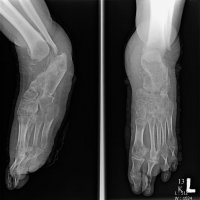

Charcot joint, also known as a neuropathic joint or Charcot (neuro/osteo)arthropathy, refers to a progressive degenerative/destructive joint disorder in patients with abnormal pain sensation and proprioception.

In modern Western societies by far the most common cause of Charcot joints is diabetes mellitus, and therefore, the demographics of patients matches those of older diabetics.

Unlike septic arthritis, Charcot joints although swollen are normal temperature without elevated inflammatory markers. Importantly, they are painless.

Charcot joints are typically unilateral but are bilateral in ~20% (range 5.9-39.3%) of cases.

In the presented case there are destruction of talar head and neck with dislocation of talo-navicular joint, resorption of midfoot bones, subchondral sclerosis and multiple subchondral cysts on talocalcaneal aspect and cuboid facet of the calcaneum, progressive decrease of calcaneal inclination with typical rocker-bottom deformity, soft tissue swelling and arterial calcification. Bony debris are seen on dorsal aspect of the foot and posterior ankle joint. All findings are suggestive of Charcot neuro-osteoarthopathy, which is primarily an articular disease and most commonly located in the midfoot.